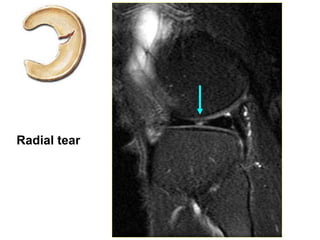

RAÙCH SUÏN CHEÂM

- Taêng tín hieäu beân trong suïn cheâm lieân

quan ñeán maët khôùp treân vaø döôùi.

- Chaån ñoaùn raùch suïn cheâm vaø daïng ñöôøng

raùch treân 3 maët phaúng Axial, Sagittal Pd

FS vaø Coronal Medic 3d. Xem suïn khôùp

treân 3 maët phaúng naøy, ñaëc bieät neân khaûo

saùt thaân suïn cheâm treân maët phaúng Coronal

beân caïnh Sagittal.

Thoaùi hoaù suïn cheâm •Raùch suïn cheâm

MRI giuùp xaùc ñònh vò trí suïn raùch vaø daïng ñöôøng

raùch:

- Vò trí raùch suïn: 1/3 trong, giöõa hay ngoaøi

- Daïng raùch:

o Horizontal tear

o Longitudinal tear

o Radial tear

o Flap tear

o Bucket handle tear

o Meniscocapsular separation

Radial tear